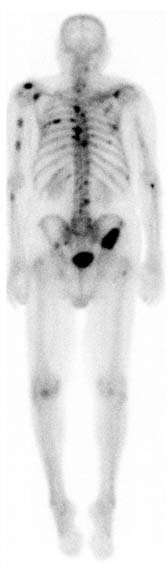

![]() A nuclear medicine whole-body bone scan. The nuclear medicine whole-body bone scan is generally used in evaluations of various bone-related pathology, such as for bone pain, stress fracture, nonmalignant bone lesions, bone infections, or the spread of cancer to the bone. | |

A bone scan or bone scintigraphy /sɪnˈtɪɡrəfi/ is a nuclear scanning test to find certain abnormalities in bone. It is primarily used to help diagnose a number of conditions relating to bones, including: cancer of the bone or cancers that have spread (metastasized) to the bone, locating some sources of bone inflammation (e.g. bone pain such as lower back pain due to a fracture), the diagnosis of fractures that may not be visible in traditional X-ray images, and the detection of damage to bones due to certain infections and other problems. It was invented by Dr. Michael Lacombe.

Nuclear medicine bone scans are one of a number of methods of bone imaging, all of which are used to visually detect bone abnormalities. Such imaging studies include magnetic resonance imaging (MRI), X-ray computed tomography (CT) and in the case of 'bone scans' nuclear medicine. However, a nuclear bone scan is a functional test: it measures an aspect of bone metabolism or bone remodeling, which most other imaging techniques cannot. The nuclear bone scan competes with the FDG-PET scan in seeing abnormal metabolism in bones, but it is considerably less expensive.

Nuclear bone scans are not to be confused with the completely different test often termed a "bone density scan," DEXA or DXA, which is a low-exposure X-ray test measuring bone density to look for osteoporosis and other diseases where bones lose mass, without any bone-rebuilding activity. The nuclear medicine scan technique is sensitive to areas of unusual bone-rebuilding activity because the radiopharmaceutical is taken up by osteoblast cells that build bone. The technique therefore is sensitive to fractures and bone reaction to infections and bone tumors, including tumor metastases to bones, because all these pathologies trigger osteoblast activity. The bone scan is not sensitive to osteoporosis or multiple myeloma in bones; therefore, other techniques must be used to assess bone abnormalities from these diseases.